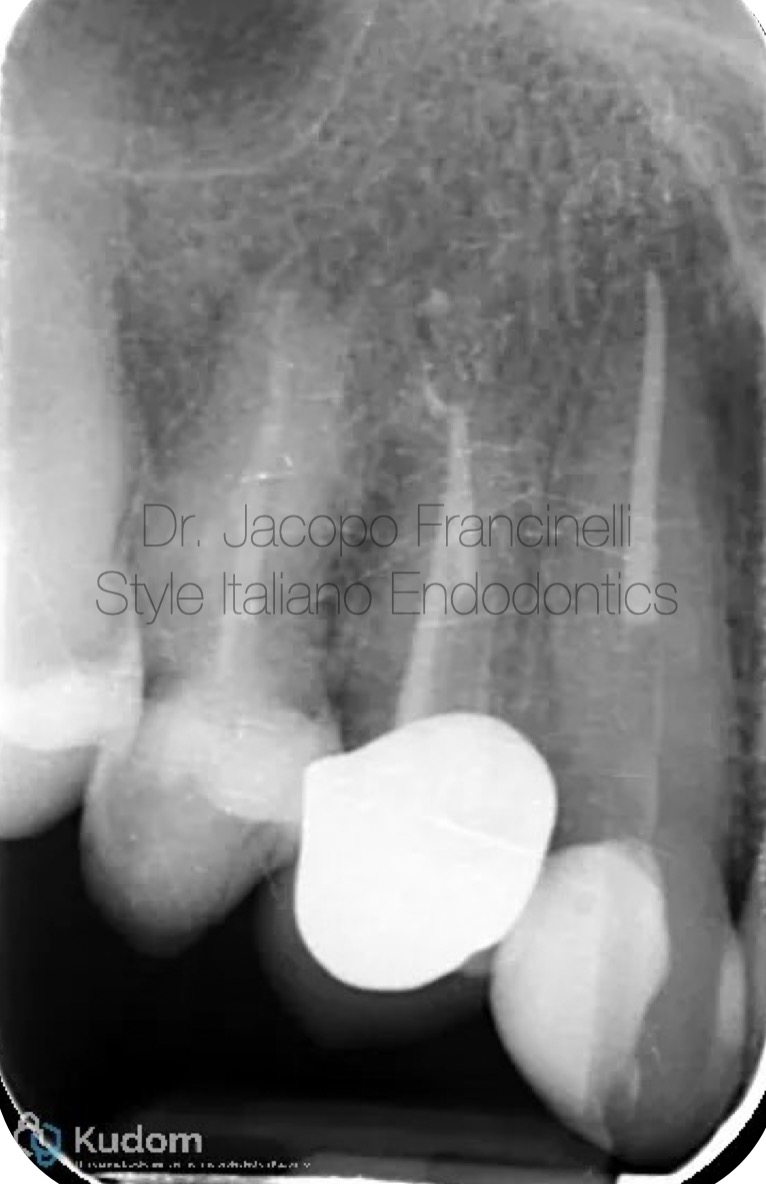

Fig. 2

Post-operative X-ray (Final Obturation and Reconstruction):

The final radiograph shows a dense and homogeneous root canal obturation extending to the correct working length, with excellent adaptation to canal walls and no visible voids.

Additionally, the image demonstrates the placement of an intracanal endodontic post within the prepared canal space. The post is well-centered and aligned with the root axis, contributing to optimal retention and structural reinforcement of the remaining tooth. This reconstruction ensures long-term stability and supports the coronal restoration, completing the endodontic treatment successfully.